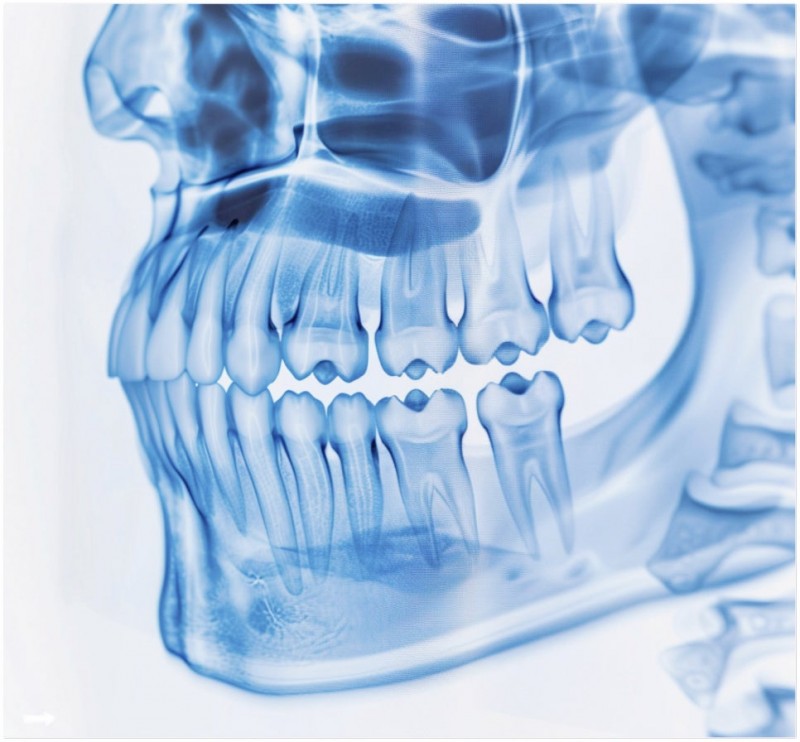

턱에서 딱딱 소리 나세요? 몸 전체가 보내는 신호일 수 있어요

01. 턱에서 소리 나는 게 정말 큰 문제일까요?

턱관절은 우리 몸에서 가장 복잡하면서도 자주 쓰이는 관절 중 하나예요.

하루에도 수천 번 움직이며 말하고, 씹고, 삼키는 동작을 도맡고 있죠.

그래서 턱에서 '딱딱' 소리가 난다면, 그냥 단순한 현상은 아닐 수도 있어요.

우리 몸의 중심축이라 할 수 있는 상부 경추, 특히 목뼈 1번과 2번이 틀어지면

이게 두개골과 척추까지 영향을 줄 수 있거든요.

일부 임상 연구에서도 턱관절 이상이 전신 불균형의 시작점이 될 수 있다는 이야기가 나오고 있어요.

특히 턱에 문제가 있는 분들 중에 목과 어깨 통증, 두통까지 함께 겪는 경우가 많은 것도 이 때문이에요.

02. 목이나 어깨가 아픈 것도 턱이 원인일 수 있나요?

네, 의외로 턱관절 이상이 목과 어깨는 물론 척추 전체에까지 영향을 줄 수 있어요.

턱관절과 경추는 해부학적으로 아주 가까운 구조에 있기 때문이죠.